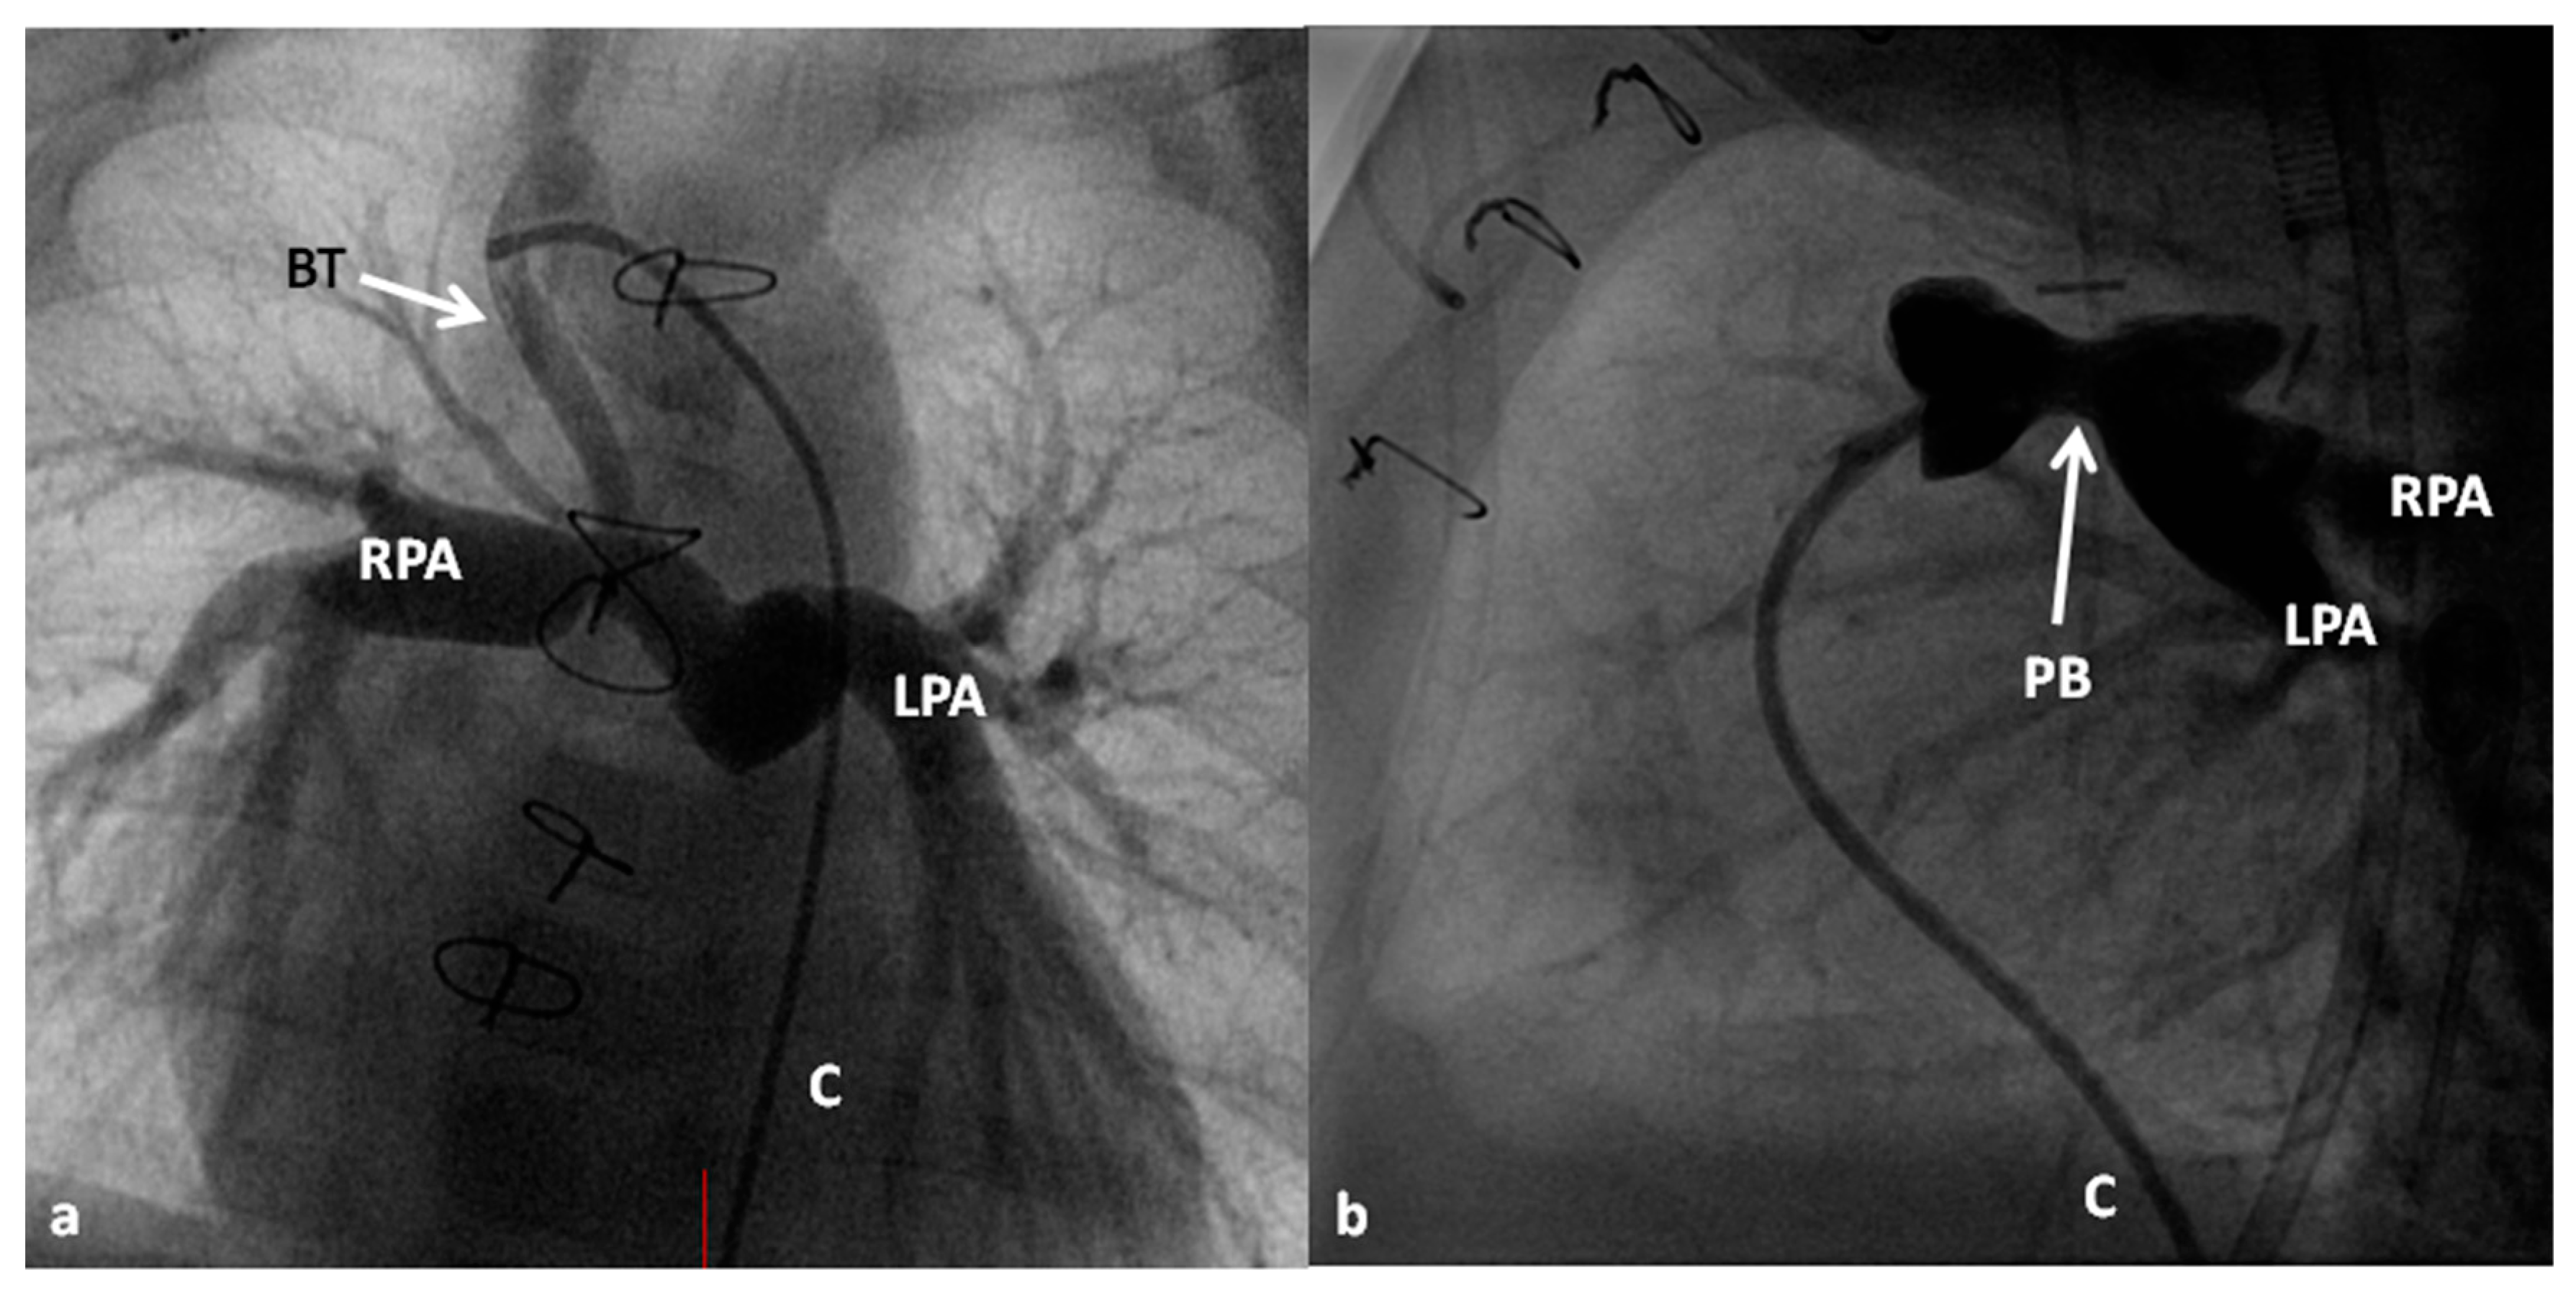

4.2.1. Stage I

At the time of presentation, usually in the early infancy, palliation depending the physiological abnormality (modified BT shunt or pulmonary artery banding) (Figure 7) is performed after initial stabilization.

4.2.2. Stage II

At about the age of six months, a bidirectional Glenn procedure [80] is performed. In this procedure, the superior vena cava (SVC) is disconnected from the right atrium and anastomosed to the PA so that the blood from SVC is directed into both branch PAs, thus the name bidirectional Glenn (Figure 8).

In patients with an additional persistent left SVC, a bilateral, bidirectional Glenn procedure (Figure 9) is performed especially if the bridging left innominate vein is small or absent.

Prior to the bidirectional Glenn procedure, normal pulmonary artery pressures should be documented either by echo-Doppler or cardiac catheterization studies. In cases with PA stenosis and mitral valve regurgitation, these abnormalities should also be repaired at the time of bidirectional Glenn procedure. Subaortic stenosis, if present, should also be bypassed by Damus–Kaye–Stansel. If there are any other hemodynamically significant abnormalities, they should also be addressed at this stage.